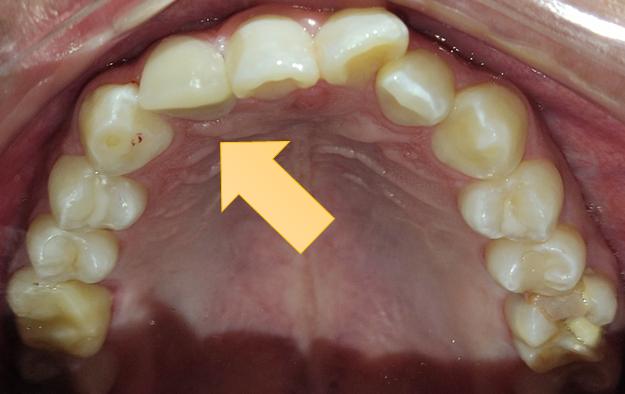

Al examen clínico intraoral se evidenció en la pieza, motivo de consulta, una alteración del desarrollo

dentario de forma, asemejando tener dos coronas en una sola pieza dentaria, unidas parcialmente en el tercio medio y cervical, delimitado por un surco central proveniente de la unión cementoesmalte, presentando una corona disto vestibular y otra mesiopalatina, hacia el borde incisal las coronas están separadas, también se evidencia a nivel del surco una caries de esmalte con cambio de coloración marrón (Fig. 1.A). A nivel de la cara palatina de la pieza 1.2 se evidencia la presencia de una cúspide accesoria en la corona mesiopalatina la misma que se denomina cúspide en garra (Fig. 1.B).

Figura Nº1 A. Fotografía intraoral en oclusión, señalando la pieza (1.2) note el surco vestibular con cambio de coloración. B. Fotografía intraoral oclusal se observa en la corona mesiopalatina la cúspide en garra.

Fuente: Elaboración propia, octubre 2021.